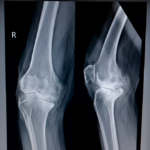

Plain radiographs obtained in the office offer a two-dimensional view of the hip or knee joint. The Mako system utilized a pre-operative CT scan to establish a three-dimensional model of the hip or knee joint that allows individualized pre-operative planning and component positioning.